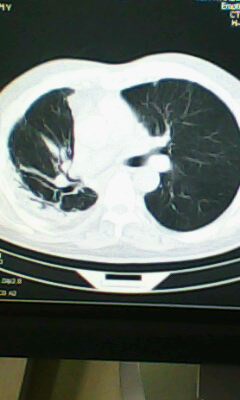

标题: CT25675:男 71 肺癌部分切除术后 3年 [打印本页]

标题: CT25675:男 71 肺癌部分切除术后 3年

两肺感染性病变,右侧肺膨胀不全,左侧上叶结节影及左侧颈部淋巴结肿大建议复查。

1)两肺感染性病变。2)右侧胸膜增厚。3)冠状动脉及主动脉钙化。

右肺炎症,左肺炎症。

右侧胸膜肥厚。

两肺感染性病变\\右侧胸膜增厚

1.右肺符合肿瘤切除术后ct表现。

2.左肺炎症。

术后改变,双肺内纤维索条影考虑与放疗有关。